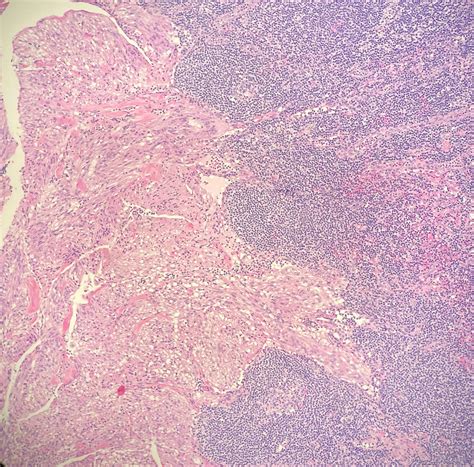

Lymph nodes are small, bean-shaped structures that play a crucial role in the body's immune system. They are part of the lymphatic system, which helps to fight infections and diseases by filtering lymph fluid and trapping foreign particles, such as bacteria and viruses. Lymph nodes are located throughout the body, with clusters found in the neck, armpits, groin, chest, and abdomen.

In the context of cancer, lymph nodes serve as a pathway for cancer cells to spread from the primary tumor site to other parts of the body. When cancer cells invade the lymphatic system, they can travel through the lymph nodes and potentially metastasize to distant organs. This is why lymph node dissection is often a key component of cancer staging and treatment.